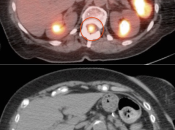

CNS Malignancy (Brain & Spinal Cord)

BRAIN:

Fast Facts:

- 2nd leading cause of death for men, ages 20-39

- 5th leading cause of death for women, ages 20-39

- Metastatic lesions are >10 times more common than primary lesions.

Tumor Grade:

While there are many types and subtypes of primary CNS malignant lesions, the PET/CT radiologist can address them as 2 groups:

- “Low-Grade”: Grades I & II (20-80% 5-year survival rate)

- “High-Grade”: Grades III & IV (4-17% 5-year survival rate)

Utility of PET/CT Scan for Primary Brain Tumors:

PET/CT is generally not used to decide whether or not a patient has a primary brain tumor (a diagnosis of brain tumor has nearly always already been made by CT or MRI prior to PET/CT scanning). The true value of PET/CT is determining whether or not a known tumor is “high-grade” or not.

- Characterizing lesions as “low-grade” or “high-grade” (with dramatic implications on management & prognosis):

- Low-Grade: Uptake ≈ white matter (may use contralateral centrum semiovale for comparison)

- High-Grade: Uptake > white matter (≈ grey matter)

- As the brain lesion may not clearly identifiable on the non-contrast CT images, it is essential to view the prior MRI (or CT) that lead to the initial diagnosis of “brain tumor”.